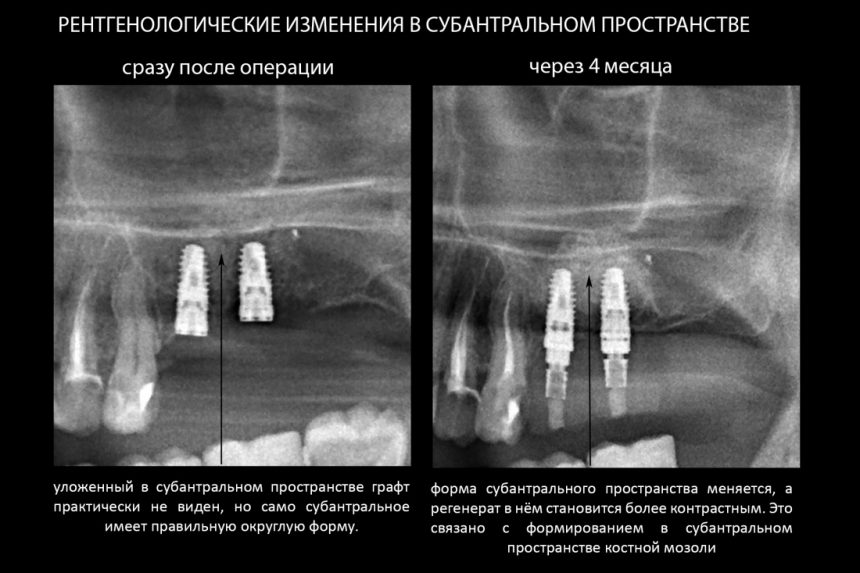

Кстати, обрати внимание на ширину альвеолярного гребня (левая картинка). Она чуть меньше 3 мм. Это объясняет, почему я засомневался в возможности установки имплантатов одновременно с остеопластикой. Понятно и без КЛКТ.

Возвращаемся к основной операционной области. Еще раз посмотрим на альвеолярный гребень, поофигеваем от его ширины и моих грандиозных планов:

Глянем на то, что получилось: